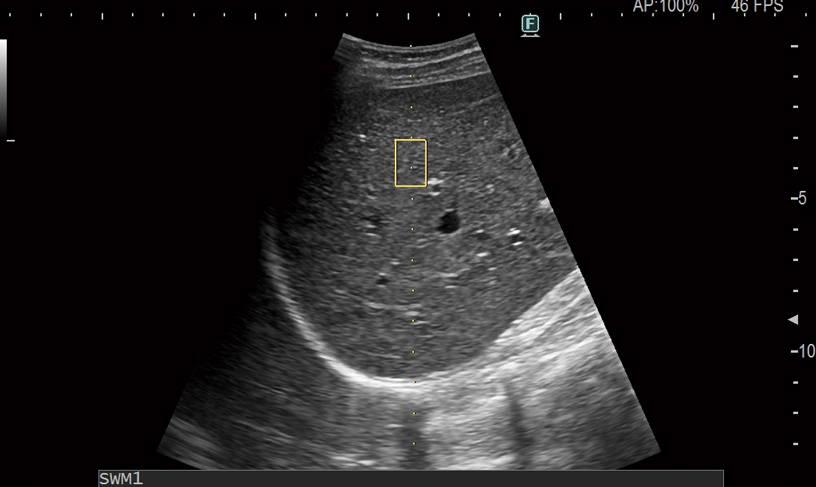

Avoid complex procedures like biopsy or MRI with our easy-to-use shear wave ultrasound features. Shear waves are generated using a ‘push pulse‘ to excite the tissues. SWM provides an assessment of tissue stiffness by calculating Vs, the propagation velocity of the shear waves. Thank to our unique reliability index, liver stiffness can be assessed with highly accurate quantitative information and reproducibility. SWE color-codes tissue stiffness based on the propagation velocity of shear waves. Both can be used to evaluate liver visually and non-invasively and enabling you to accurately stage the level of fibrosis.Furthermore, ATT measurement, to score the level of fatty infiltration, using the attenuation coefficient, is combined with Shear Wave Measurement for a complete multiparametric approach to chronic liver disease management.